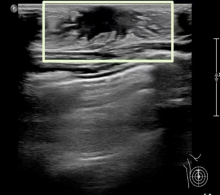

Tanner II期 乳晕后方呈星形或线样低回声区(白色方框)